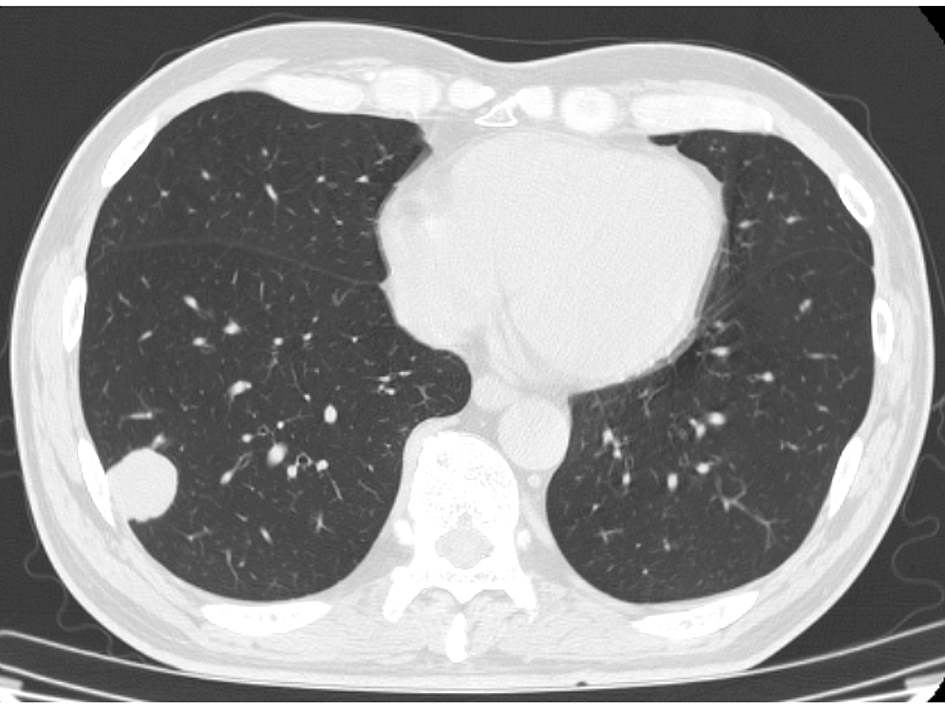

The blood test showed liver dysfunction and pre-renal dehydration. The circulating white blood cells were 13,440 cells/mL, hemoglobin was 12.4 g/dL and the platelet count was 27.8 × 104 cells/μL. The chemistry panel showed a potassium level of 5.1 mmol/L, chloride of 99 mmol/L, phosphate of 3.6 mg/dL and elevated levels of lactate dehydrogenase (LDH), aspartate aminotransferase (AST), alanine aminotransferase (ALT), alkaline phosphatase (ALP), total bilirubin (TB), direct bilirubin (DB) and C-reactive protein (CRP). Computed tomography and MRI revealed disseminated metastatic changes in lumbar spinal (Fig. 1), well-defined pulmonary tumors in the right lower and left upper lobes (Fig. 2) and an ambiguously bordered low-density area of the liver, predominantly in the left lobe as well as a moderate volume of ascites (Fig. 3).

![]() Click for large image | Figure 2. Chest CT. A well-defined right lung tumor of 25 mm in diameter. |